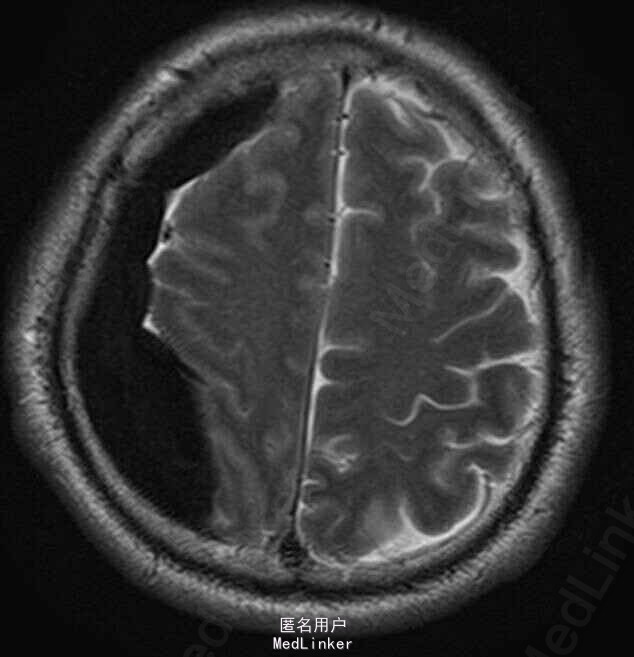

中年男性,明确外伤史;以外伤后头痛起病,MRI提示右颞顶部急性硬膜下出血;

查体:神清,遵嘱,E4V5M6,双侧瞳孔等大正圆,对光敏; 头颅MRI提示:右侧额颞顶部硬膜下血肿(急性期),中线左移位约9.2mm。

右侧额顶硬膜下血肿诊断明确。出血量较大(>30ml),有手术指征,患者手术愿望强烈,行右额颞顶慢性硬膜下血肿钻孔引流术